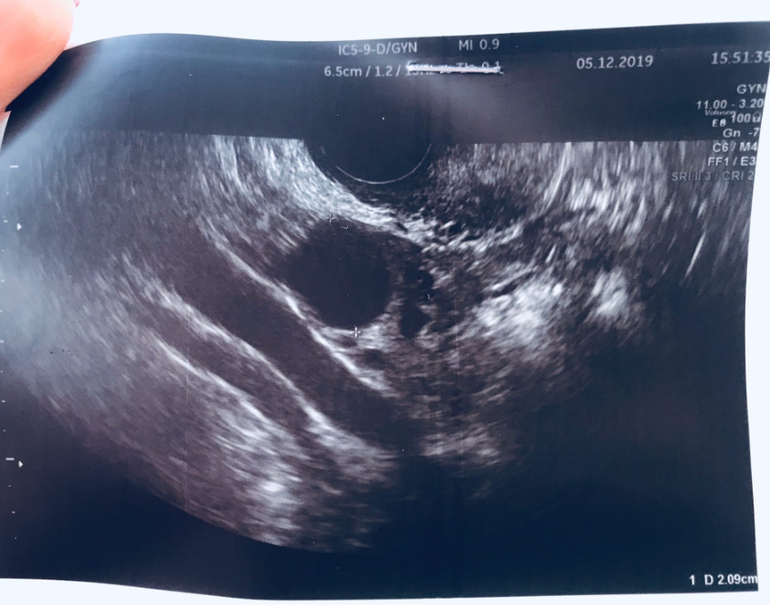

Вторая стимуляция, результаты

Вот такие мои фолики выросли на 16 ДЦ)) в ПЯ 18мм и 28мм, в ЛЯ 21мм😍Колю укол ХГЧ (5-6.12) в общей сумме 10 тыс.ед.и начинаем любовный марафон)) Купила 10 дешевых тестов, с 07.12 буду отслеживать выход укола и надеяться на появление своих //🙏